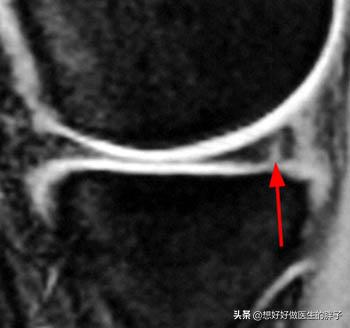

●C纵裂:这种情况由于损伤的位置,主要位于半月板的滑膜缘,这里是有血供的,这种撕裂往往有自我愈合的可能,这种情况在核磁上的表现是这个样子的

●D桶柄裂:大家仔细看这个撕裂的方式,是不是有点类似于我们在农村提的水桶的桶柄,所以我们称之为桶柄裂,也有人称之为提篮伤,核磁上是这样子的。大家细看红色的就是半月板,发生桶柄撕裂的两个部分,两个部分已经离家出走了,怎么可能自我愈合呢?和绿色的正常部分对比,大家就会发现巨大的区别。